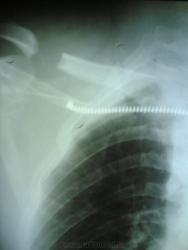

На Васильевском острове с крыши на мужчину упал кусок льда.Перелом правой ключицы,1го ребра,Th9.Параплегия нижних конечностей.

При компрессии такой степени (если перелом свежий) должны быть видны отломки. А натёчник, похоже, есть. Хотя снимки не очень… на Васильевском могли бы и лучше снять. Ещё здесь виден очень редкий сам по себе перелом I ребра.